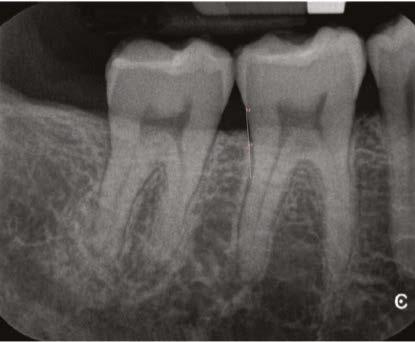

From here (Figure 6), I could see that my gutta percha was slightly overextended so I trimmed my master cones a bit prior to permanently obturating the teeth here.

Figure 5

There was some sealer extrusion at the apex of these teeth (Figure 7), especially 10, but this was due to the inflammatory resorption occurring at the apex as a result of the trauma, which started to eat away the apical stop. I am confident that, over time, this sealer will resorb away, and this extrusion should not impede the healing at all. Figure 8 is the final outcome of the case.